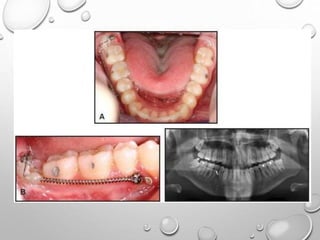

Lingual split-bone technique.

A. Outline of the incision, B. Reflection of the flap & creation of an anterior

vertical stop, C. Removal of buccal plate to expose the crown. D, Placement

of a chisel to section the lingual cortex, E. Elevation of tooth, F. Wound

closure